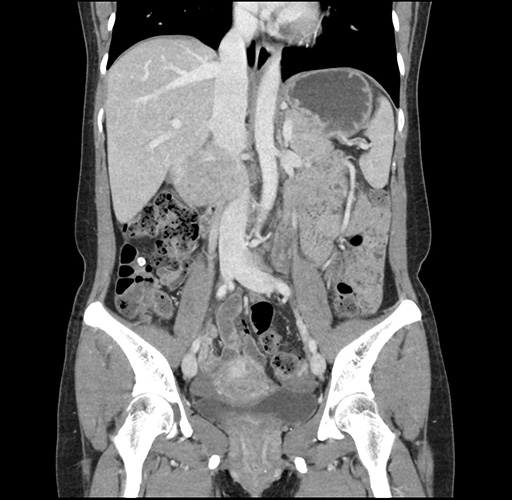

Imaging Analysis

Look through the patient's CT scan to identify any areas of concern for the necessary procedure.

Based on your CT findings, which issue(s) would give reason for "planned slowing down moment(s)" in this case?

Considering a standard left lateral sectionectomy procedure, what step(s) of the operation would you do differently in this case ?